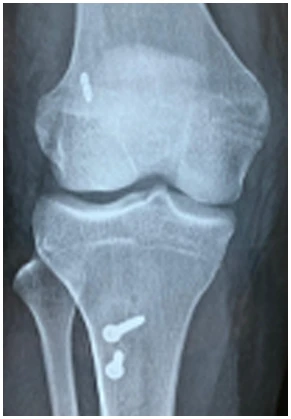

As osteotomias são procedimentos cirúrgicos que envolvem o corte e reposicionamento dos ossos ao redor da articulação do joelho para corrigir deformidades angulares, como a osteoartrose em estágio inicial ou instabilidade ligamentar. Esse procedimento visa redistribuir as forças na articulação do joelho e aliviar a pressão sobre as áreas danificadas da cartilagem.